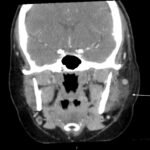

A 36-year-old immunocompetent female presented to the emergency department (ED) with five days of headache and left-sided facial pain. Physical exam showed conjunctival injection of the left eye with multiple vesicular lesions distributed along the V1 dermatome. Labs were remarkable for mild elevation in erythrocyte sedimentation rate (ESR) and c-reactive protein (CRP) with no elevation in white blood cell (WBC) count. Computed tomography (CT) with contrast of the neck revealed soft tissue stranding around the parotid gland. The patient was diagnosed with herpes zoster ophthalmicus (HZO) with concurrent ipsilateral parotitis and subsequently treated with valacyclovir, ofloxacin eye drops, topical erythromycin ointment and amoxicillin/clavulanic acid. Upon follow-up ten days after discharge, the patient noted marked improvement in her symptoms and reduction in pain. To our knowledge, this is the first case described in medical literature of a female patient with HZO and ipsilateral parotitis.